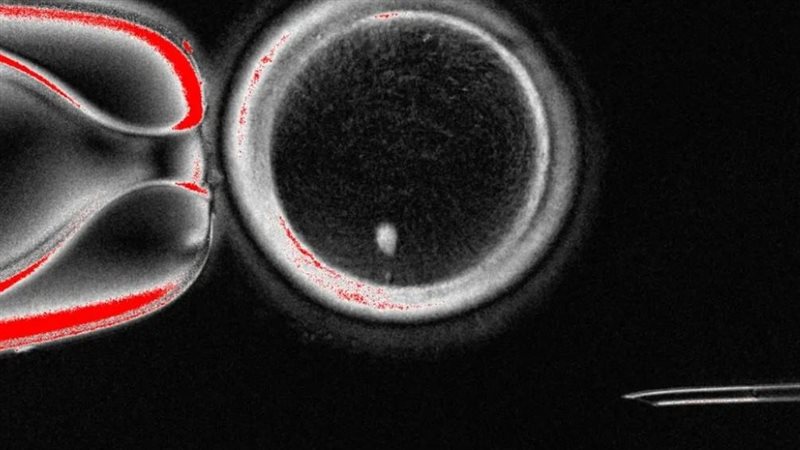

قام الباحثون باستخراج النواة من خلية الجلد البشرية، والتي تحتوي على نسخة كاملة من المادة الوراثية للفرد.

أُدخلت هذه النواة في بويضة متبرعة أُزيلت منها مادتها الوراثية، والنتيجة بويضة مزوَّدة بكامل الحمض النووي اللازم لبدء الحياة.

بخلاف البويضة الطبيعية، التي تحمل نصف الحمض النووي البشري فقط، تحتوي هذه البويضة المُعاد بناؤها على مجموعة كاملة من الكروموسومات، ولتحضيرها للتلقيح، يجب على العلماء إزالة نصف هذه الكروموسومات في عملية أطلقوا عليها اسم "الانقسام المتساوي"، وهي عملية تجمع بين مبادئ الانقسام المتساوي والانقسام المنصف. الهدف هو محاكاة بويضة طبيعية تحمل 23 كروموسومًا من كل من الوالدين، ومع ذلك، لا تزال العملية تجريبية: تتخلص البويضة من الكروموسومات عشوائيًا، مما يؤدي إلى بعض الأخطاء حيث تتضاعف بعض الكروموسومات بينما تفقد أخرى.

نجحت دراسة جامعة ولاية أوريغون للصحة والعلوم، المنشورة في مجلة نيتشر كوميونيكيشنز، في إنتاج 82 بويضة سليمة باستخدام هذه التقنية. خُصبت بعض هذه البويضات بالحيوانات المنوية، وتطورت إلى أجنة في مراحلها المبكرة، على الرغم من أن أياً منها لم يتجاوز ستة أيام من النمو.